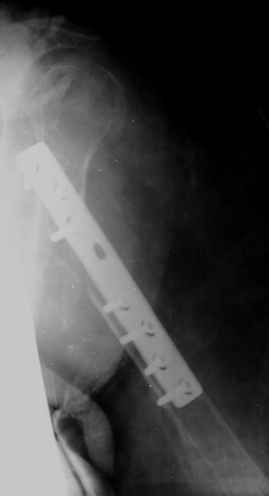

Уважаемые коллеги! На консультации больная 65 лет. С одной рентгенограммой - рис.1.

Анамнез: 30 августа перелом левой плечевой кости, невропатия лучевого нерва - кисть повисла сразу. Лечение по месту жительства - иммобилизация косынкой. 2 октября в одной из больниц города металлоостеосинтез. Все развалилось. 16 октября - повторная операция, через десять дней - картина на рис.1. Далее металлоостеосинтез с костной аутопластикой малоберцовой костью 9 февраля 2009г. Снимки 2-4 выполнены сегодня.

Считаем, что шансов на приживление и перестройку такого трансплантата в данной ситуации нет. Нестабильность запрограммирована и вываливание этого всего дело ближайшего будущего.Вопросы для обсуждения: